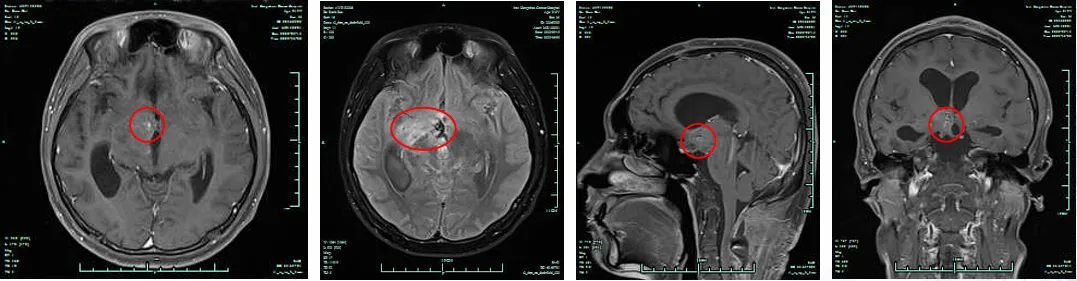

图1. 放疗前头颅MRI检查结果(2022.7.20)

(一)替莫唑胺化疗同步放疗:2022年7月11日至2022年7月22日2022年7月11日起行口服替莫唑胺280mg化疗,每日一次(QD)。7月20日、7月22日,分别行放疗前头颅、脊髓MRI检查,结果示:疾病进展(PD),颈椎、胸椎、腰椎、骶椎相应脊膜继发恶性肿瘤。